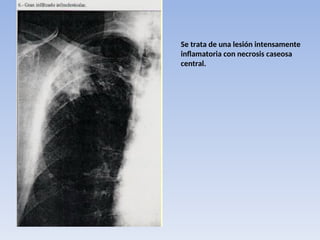

Infiltrado precoz tuberculoso

• Esta forma de tuberculosis es la más frecuente

en el adulto. La imagen del infiltrado precoz

suele ser de 3-10 cm de diámetro, tiene unos

límites imprecisos y borrosos y su localización

preferentemente es a nivel subclavicular.

Se trata de una lesión intensamente

inflamatoria con necrosis caseosa

central.

Infiltrado precoz tuberculoso •Esta forma de tuberculosis es la más frecuente en el adulto. La imagen del infiltrado precoz suele ser de 3-10 cm de diámetro, tiene unos límites imprecisos y borrosos y su localización preferentemente es a nivel subclavicular.

Se trata deuna lesión intensamente inflamatoria con necrosis caseosa central.